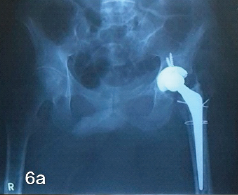

Neglected Bipolar Hemiarthroplasty Dislocation in a Young Adult with Superior Acetabular Wall Defect – A Case Report

Muni Srikanth Iytha , Vineet Thomas Abraham , Kalyan Deepak Sreenivas , Rambabu Lavudi , Showry Abraham Salikity , Praveen Goutham

Complex Reconstruction of Post-traumatic Fracture Dislocation Hip: The Anchor Total Hip Arthroplasty Following Failed Index Surgery

Vijay G Goni , Deepak Kumar , P K Vivek , Manjunath Nishani , M Harshith , V S Sumukha ………………………………p.182-187